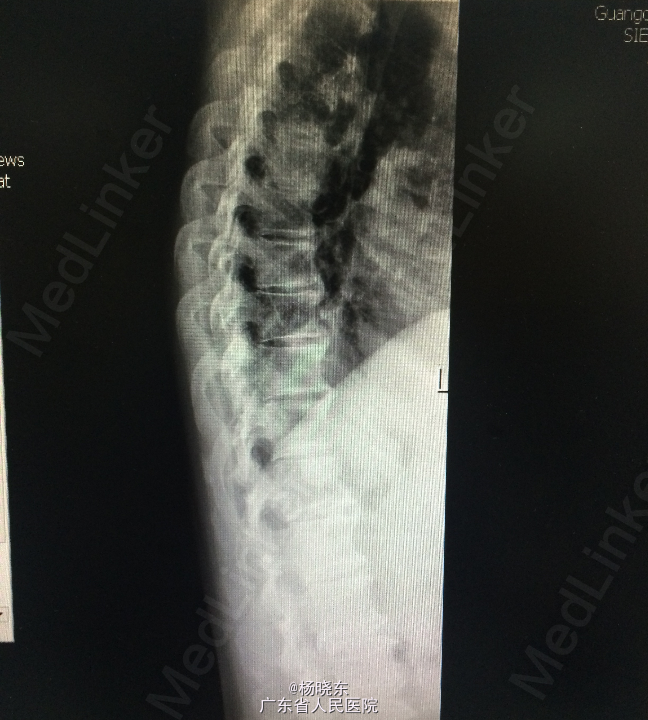

查体:贫血貌,心肺腹查体无特殊。 辅查: 1.全长双下肢长骨正位+尾椎正侧位+肋骨正位+右关节正位+骨盆正位+腰椎正侧位+下胸椎正侧位放射常规照片示:考虑多发性骨髓瘤(多发骨病变)。1、颈椎退行性变 2、腰椎退行性变;多个椎间盘病变;L1椎体轻度压缩性骨折。3、胸椎退行性变。 2.骨髓活检:可见少许造血成分,粒红比例大致正常,均以中晚幼阶段细胞为主,全片可见三个巨核细胞,形态未见明显异常。并可见浆细胞散在。 3.骨髓-外周血涂片:MM-骨髓增生活跃,浆细胞占58.0%,其中原幼浆占53.5%,外周血占2.0%。